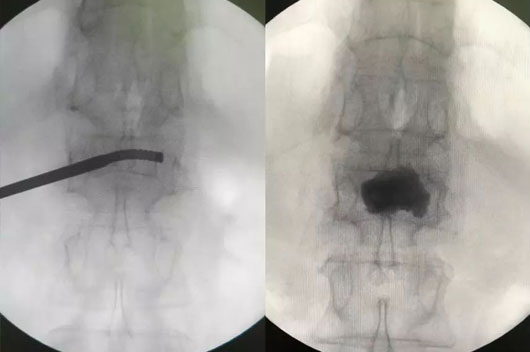

´Ë´ÎÊÖÊõʹÓûúеÈËÍýÏëµ¥²à´©´ÌÑü1×ó²àõè¾¶£¬£¬£¬ £¬£¬£¬£¬£¬Çпª0.5cmƤ·ô£¬£¬£¬ £¬£¬£¬£¬£¬ÔÚ»úе±ÛÖ¸µ¼Ï¾«×¼ÖÃÈëµ¼Õ롢ͨµÀÖÁ×µÌåÄڵİÐλÖ㬣¬£¬ £¬£¬£¬£¬£¬°²ÅÅ¿ÉÍäÇúÇòÄÒ¾ÙÐж¨µãÀ©ÕÅÅòÕÍ£¬£¬£¬ £¬£¬£¬£¬£¬Ë³ËìÍê³É¿ÉÍäÇúµ¥²àPKPÊÖÊõ£¨Í¼1-4£©¡£¡£¡£¡£¡£

ͼ3£¬£¬£¬ £¬£¬£¬£¬£¬ÍÆ×¢¹ÇË®Äà

4.jpg

ͼ4£¬£¬£¬ £¬£¬£¬£¬£¬µ¥²à´©´ÌÖÁ×µÌå¶Ô²à½¨É軡ÐÎͨµÀ£¬£¬£¬ £¬£¬£¬£¬£¬¹ÇË®ÄàÂþÑÜÓÅÒì